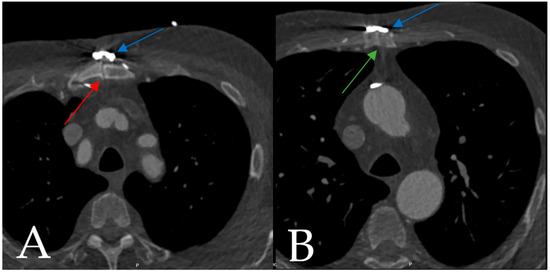

4.1.1. Case 1

4.1.2. Case 2